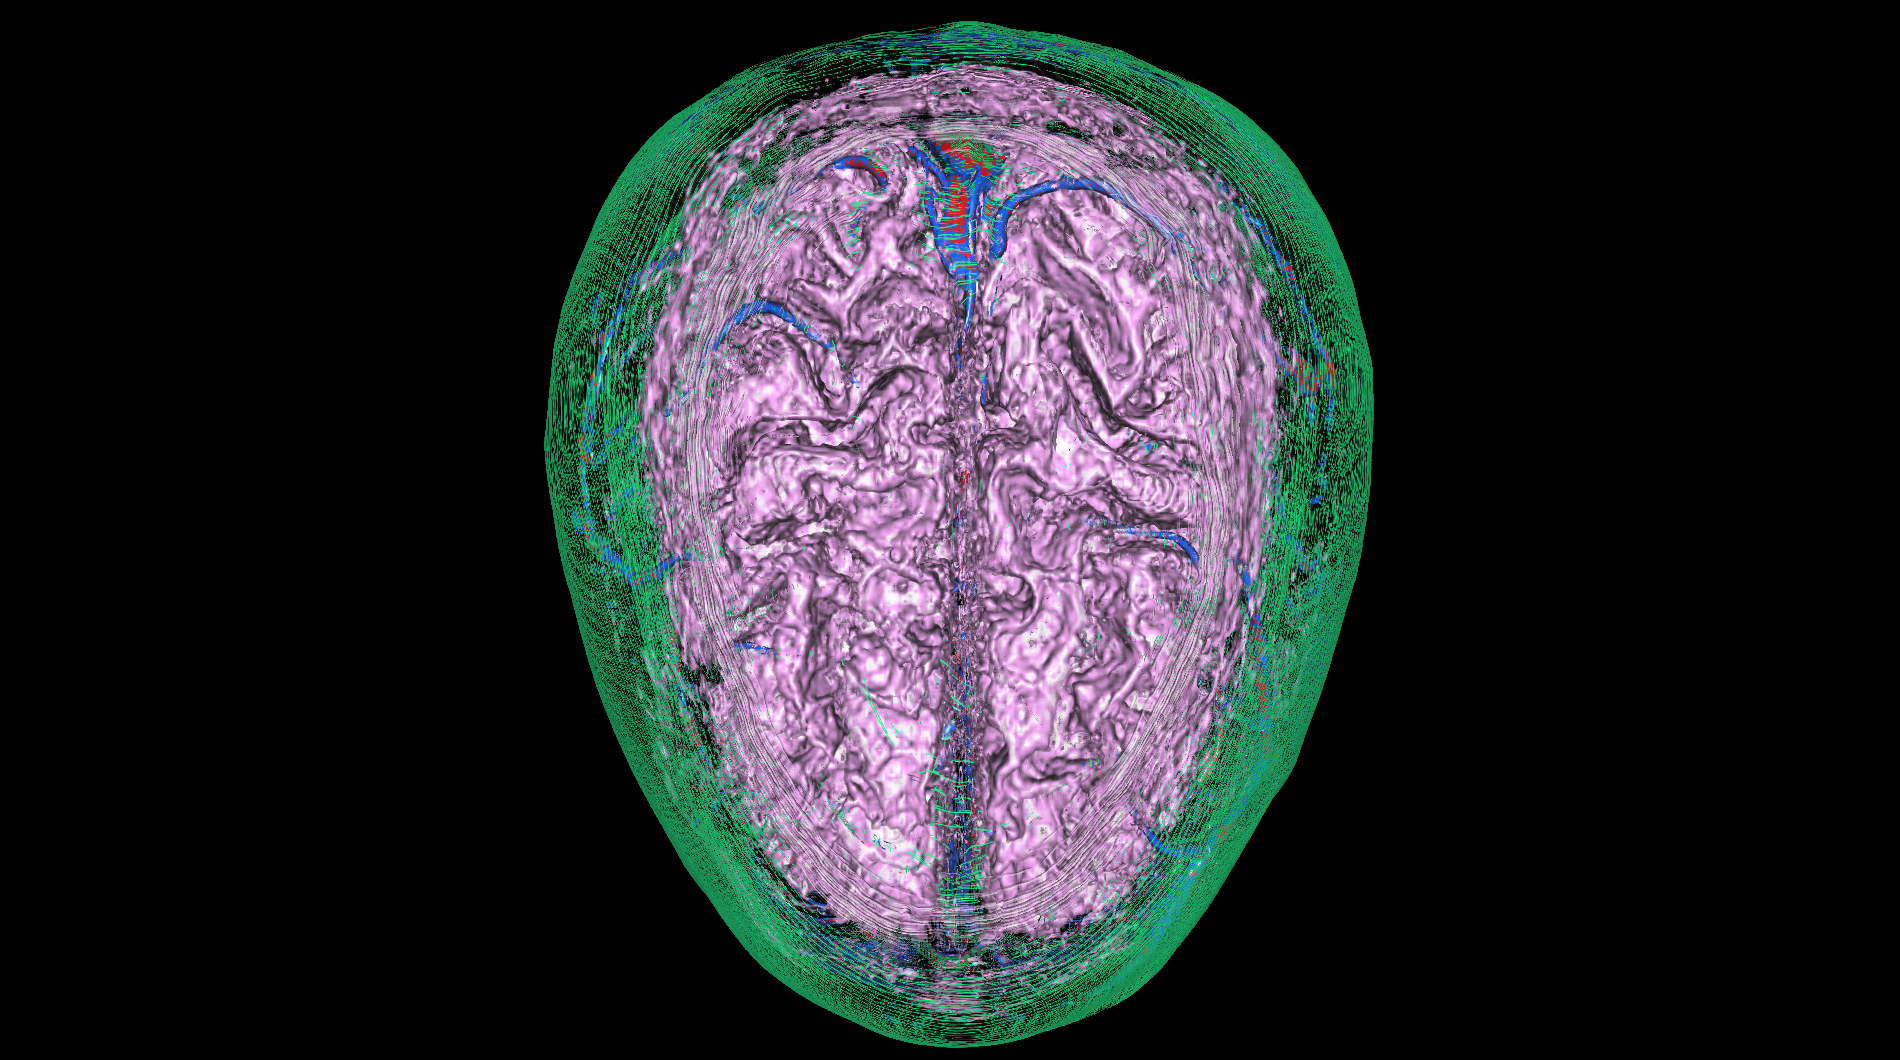

| The medical-04 workload evaluates medical visualization techniques using the Tuvok library and OpenGL API. It features slice rendering and raycasting with 1D and 2D transfer functions, exploring datasets from a beating heart, brain, and alligator. Clipping planes and varying voxel densities test performance in medical imaging workflows, simulating scenarios like MRI and CT analysis. | |||

| Composite Score: | 271.71 | ||

| Graphics Renderer: | RTX 6000 Ada Generation | ||

| Index | Description | Weight | Result (FPS) |

Raycasting of a brain with 2D transfer

Raycasting of a brain with 2D transfer

|

10.00 |

416.83

|

| 6 |

Raycasting of a brain with 2D transfer and clipping plane

Raycasting of a brain with 2D transfer and clipping plane

|

10.00 |

947.32